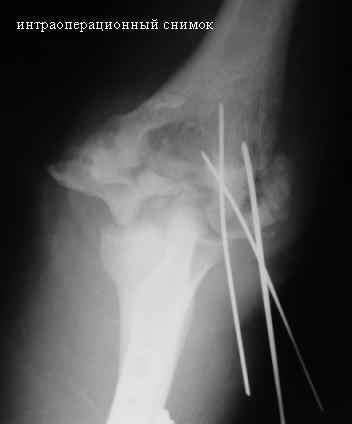

Стойкая комбинированная контрактура правого локтевого сустава

Увжаемые коллеги! На консультации больной со стойкой комбинированной контрактурой правого локтевого сустава.

В прошлом - спортсмен, сейчас охранник. Травма 2 августа 2008г., автодорожная. Оперирован в одной из больниц города. Остеосинтез, два месяца гипс. Объем движений с тех пор не изменился. Боли после физнагрузки (пытается тренироваться).